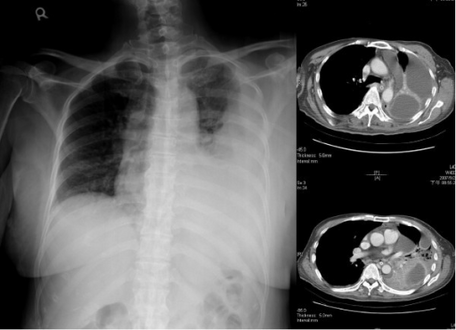

An empyema (/ˌɛmpˈmə/) is a collection of pus within a naturally existing anatomical cavity. For example, pleural empyema is empyema of the pleural cavity. It must be differentiated from an abscess, which is a collection of pus in a newly formed cavity. The term is from Greek ἐμπύημα, "abscess".

Lungs[edit | edit source]